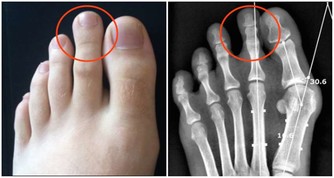

超聲科醫師檢查發現其右側陰囊空虛,右側腹股溝內可見大小約2*2*1cm的類睾丸迴聲,診斷考慮:隱睾症。

目前超聲檢查是最簡便,快捷無創的檢查方法,它不僅可檢查隱睾所在的位置,還可測量隱睾大小。